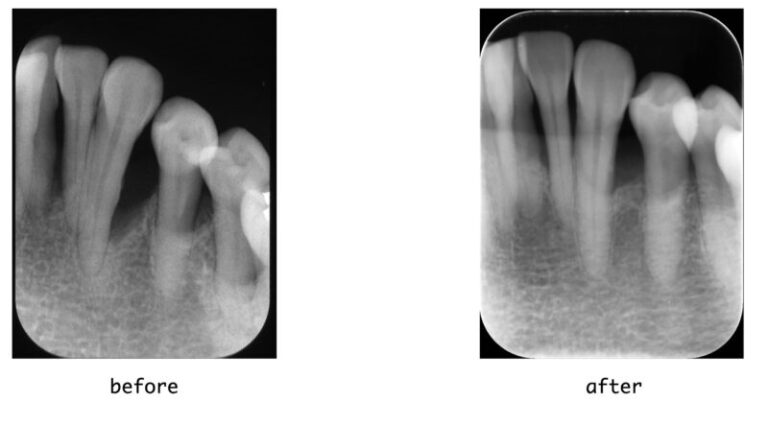

【症例】重度歯周炎に対する歯周組織再生療法(エムドゲイン・骨移植)

【症例】重度歯周炎に対する歯周組織再生療法(エムドゲイン・骨移植) 患者様 60代 女性 主訴(来院理由) 検...